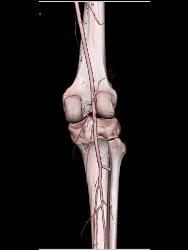

Patent Popliteal Artery and Trifurcation